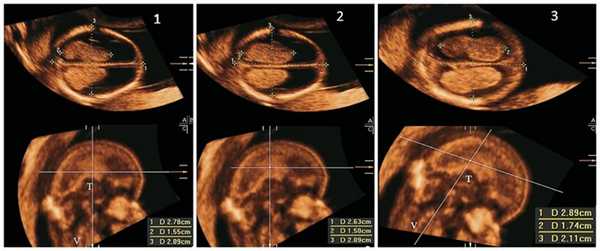

На офтальмоскопии выявлены застойные явления на глазном дне справа и слева. По данным магнитно-резонансной томографии (МРТ) головного и спинного мозга с внутривенным контрастированием в последовательности MPRAGE, толщиной среза 1 мм на фоне выраженной внутренней гидроцефалии в заднем роге правого бокового желудочка выявлен опухолевый узел в виде «цветной капусты» на сосудистой ножке, размером 33×20×24 мм, гипоплазия червя мозжечка, mega cisterna magna, которая широко сообщается с IV желудочком (вариант мальформации Денди-Уокера) (рис. 1).

Рисунок 1. Данные МРТ головного мозга с внутривенным контрастированием до проведения операции. а - сагиттальный срез: 1 - mega cisterna magna, сообщающаяся с IV желудочком (вариант мальформации Денди-Уокера). Отмечается гипоплазия червя мозжечка; б - аксиальный срез: 2 - опухолевый узел в виде «цветной капусты» на сосудистой ножке, расположенный в заднем роге правого бокового желудочка, на фоне выраженной внутренней гидроцефалии; в - сагиттальный срез: 3 - сосудистая ножка опухоли. В анализе ликвора (пункция помпы ВПШ) цитоз 13 клеток (лимфоцитов 8, нейтрофилов 5), белок 0,62 г/л, хлор 116 ммоль/л, глюкоза 3,25 ммоль/л. Для дополнительной визуализации сосудистой ножки опухоли выполнена КТ с ангиографией и 3D-реконструкцией (рис. 2). Рисунок 2. Данные КТ ангиографии с 3D-реконструкцией. а - вид спереди: 1 - опухоль; б - вид сверху: 2 - сосудистая ножка опухоли (венозный компонент которой формируется из таламостриарной вены), 3 - таламостриарная вена; в - вид сбоку: 1 - опухоль расположенная в заднем роге бокового желудочка, 2 - сосудистая ножка опухоли. 05.08.11 проведена операция: эндоскопическое тотальное удаление хориоидпапилломы правого бокового желудочка. Клипирование сосудистой ножки опухоли. Проба Арендта. Удаление ВПШ (хирург - д.м.н., проф. А.А. Суфианов). Операция выполнена в положении ребенка на спине с мягкой фиксацией головы в раме DORO (PMI, Германия). Использовался комплект для эндоскопических операций на головном мозге (Gaab KARL STORZ, Германия), оптика HOPKINS II Karl Storz (0°, 30°, 45°). Выполнен операционный доступ парасагиттально справа в теменной области через фрезевое отверстие. Через нейроэндоскоп визуализирована опухоль, расположенная в заднем роге бокового желудочка, и ее сосудистая ножка. Сформирован второй операционный доступ в теменной области справа, введен дополнительный эндоскопический порт 6 мм («Johnson&Johnson», XCEL ENDOPATH) (рис. 3). Рисунок 3. Начальный этап операции - установка эндоскопических портов. 1 - дополнительный эндоскопический порт для микроинструментов; 2 - основной эндоскопический порт нейроэндоскопа. С помощью биполярной коагуляции проведено выделение сосудистой ножки для клипирования. Эндоскопическим клипатором сосудистая ножка клипирована титановыми клипсами и пересечена. Опухоль удалена кускованием через дополнительный эндоскопический порт (рис. 4). Рисунок 4. Основные этапы эндоскопического бипортального удаления хориоидпапилломы. а - основные анатомические интравентрикулярные ориентиры в теле желудочка: 1 - отверстие Монро, 2 - таламостриарная вена, 3 - таламус; б - основные анатомические интравентрикулярные ориентиры в заднем роге бокового желудочка: 4 - сосудистая ножка опухоли, 5 - область треугольника заднего рога бокового желудочка, 6 - височный рог; в - общий вид опухоли (7). Стрелками обозначены визуализированные при вентрикулоскопии микрокальцинаты в опухоли; г - сосудистая ножка опухоли: 8 - венозный компонент, 9 - артериальный компонент; д - этап введения дополнительного эндоскопического порта и его расположение по отношению к опухоли: 10 - эндоскопический порт, 11 - опухоль; е - коагуляция мелких сосудов в структуре сосудистой ножки опухоли: 12 - эндоскопический коагулятор, 13 - след от коагуляции сосудов; ж - частичная диссекция сосудистой ножки опухоли: 14 - микродиссектор; з - после микродиссекции введен эндоскопический клипатор с несъемными клипсами (15); и - этап наложения клипсы (16) на сосудистую ножку; к - клипированная сосудистая ножка; л - пересечение клипированной сосудистой ножки микроножницами (17); м - клипса на культе сосудистой ножки. Кровопотеря составила 10 мл, большая часть которой приходилась на кожные разрезы. После проведения пробы Арендта (положительная) ВПШ удален. Послеоперационный период протекал удовлетворительно. После операции проведена КТ головы, данных о кровоизлиянии нет. На контрольной МРТ и КТ с 3D-реконструкцией черепа с внутривенным контрастированием состояние после тотального удаления опухоли сосудистого сплетения правого бокового желудочка, сосудистая ножка клипирована. Открытая внутренняя гидроцефалия прежних размеров (рис. 5). Рисунок 5. Данные МРТ головного мозга и КТ-ангиографии с 3D-реконструкцией после операции. а - аксиальный срез МРТ, опухоль тотально удалена: 1 - артефакт от сосудистой клипсы; б - сагиттальный срез МРТ. Обозначение то же, что и на рис. а; в - вид спереди, опухоль тотально удалена: 2 - место расположения опухоли до ее удаления.